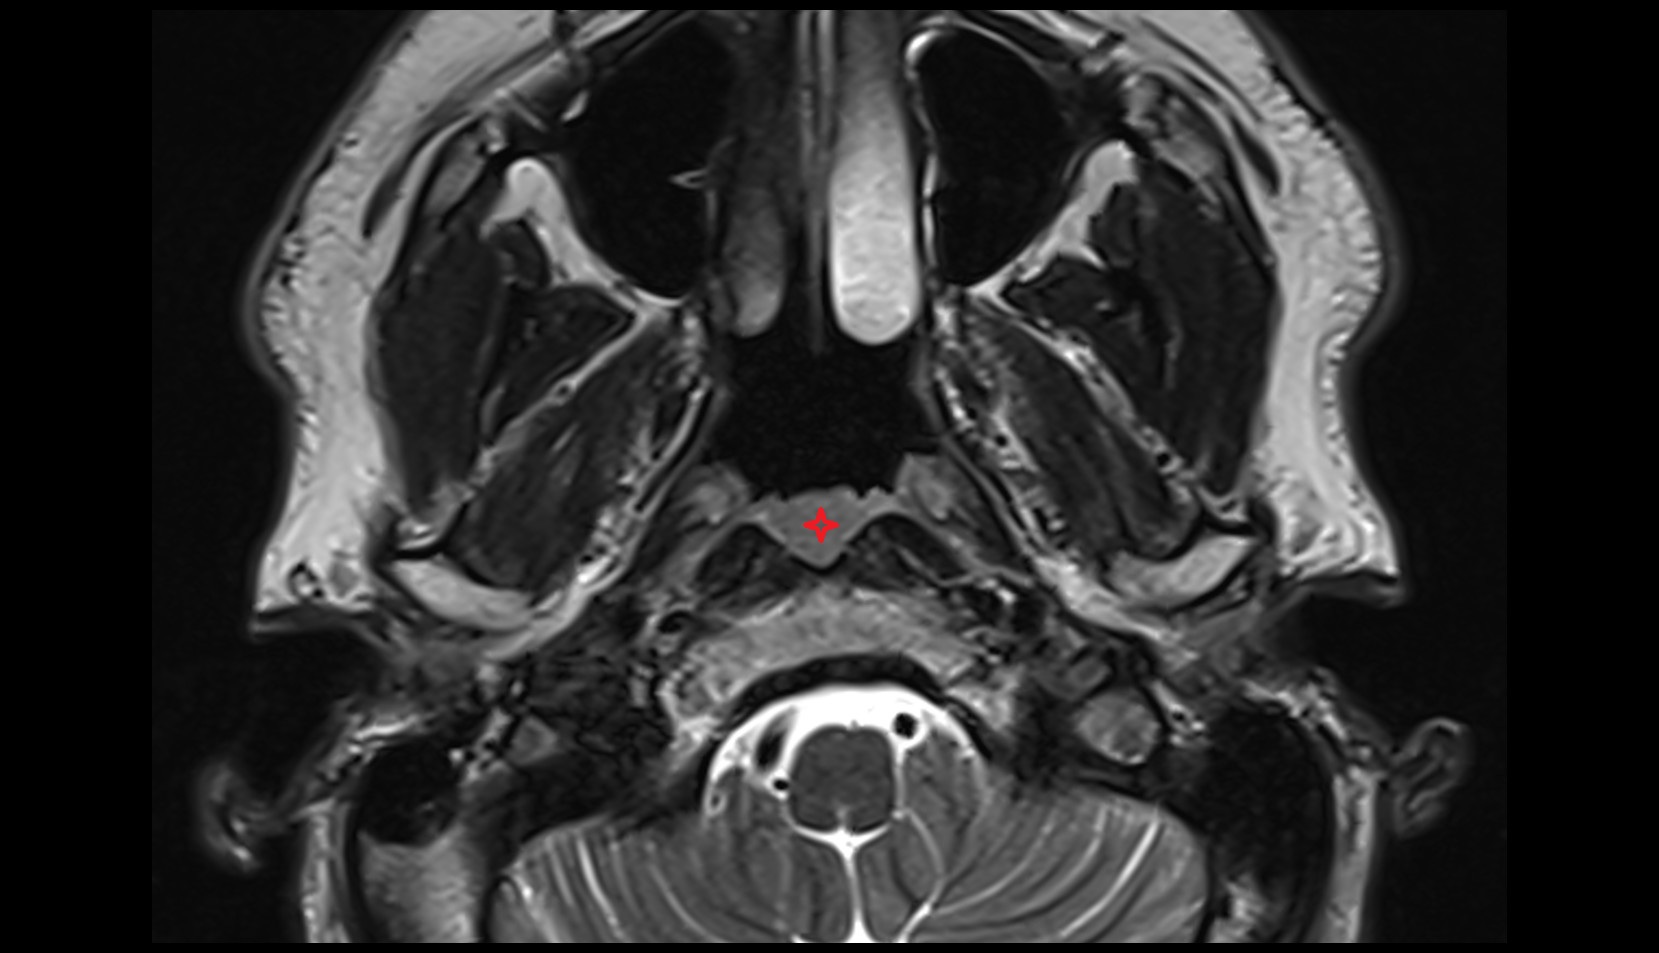

- Temporomandibular joint

- Mandibular condyle

- Mandibular fossa

- Mastoid process

- Petrous part of temporal bone

- Ramus of mandible

- Squamous part of temporal bone

- Zygomatic process of temporal bone